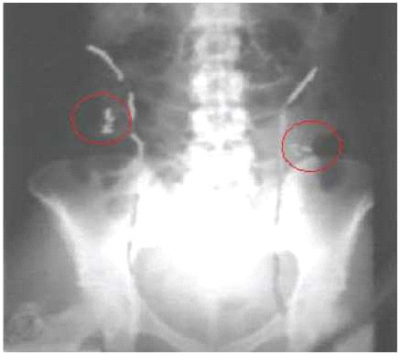

אם צפויה קרינה ישירה לאזור האגן, ניתן לבצע הסטת שחלות בניתוח זעיר פולשני (Laparoscopic surgery). בשיטה זו מקבעים את שתי השחלות גבוה, בגבול העליון של עצמות האגן, על ידי תפר או מאחורי הרחם. חשוב לדעת לפני ההליך את שדה הקרינה המיועד על מנת להוציא את השחלות מחוץ לאזור זה. במהלך ההסטה נשמרת אספקת הדם לשחלות. במקרים רבים תיתכן נפילת השחלות חזרה למקומן המקורי, ולכן, רצוי לבצע ניתוח בסמוך ככל האפשר למועד ההקרנה (תמונה 2).

חסרונות השיטה:

- צורך בניתוח

- כישלון בקיבוע ובאי-חשיפת השחלות לקרינה

- פגיעה בכלי דם הגורמת לפגיעה בשחלה והפסקת תפקודה

- היווצרות כיסתות (Cysts) שחלתיות

- סיכוי נמוך מאוד להיריונות עצמונים ובדרך כלל יש צורך בשימוש בהפריית מבחנה בעתיד לצורך היריון. בשל גורמים אלה מדווח על שיעור גבוה של כשלונות, 50-30 אחוזים, ולכן מומלץ לשלב את הניתוח עם הקפאת רקמת שחלה